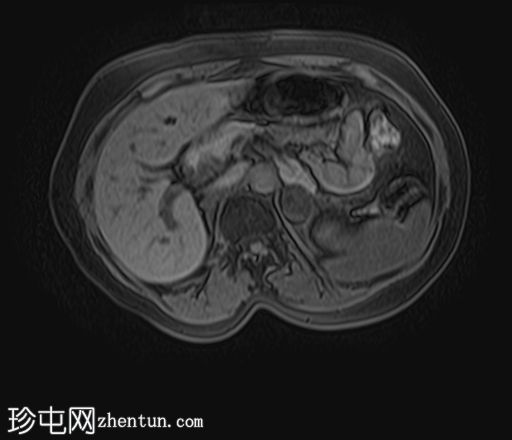

MRI

轴位T2加权像

STIR(FASE)序列

轴位

T2加权像

左侧肾上腺可见一边界清晰的病灶,大小约为3.0 × 2.4 × 2.0 cm。

化学位移成像显示,反相图像的信号强度较同相图像明显降低,与细胞内脂质含量相符。

右肾先天性缺失。左肾轻度肥大,信号强度正常。

肾上腺腺瘤的典型表现,反相成像可见明显的信号丢失。